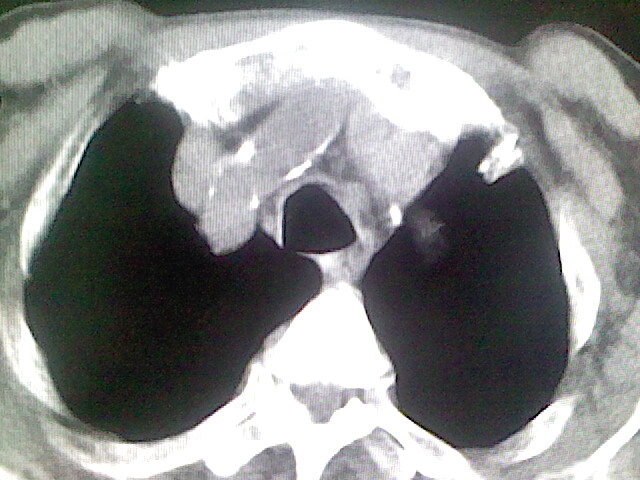

以下是引用zsl6918在2008-8-28 16:49:00的发言:[br]双肺炎性病灶,食管狭窄估计与心房增大压迫所致。

以下是引用xulianj在2008-8-28 20:36:00的发言:[br]慢支肺气肿伴感染,右上肺陈旧性结核;食道建议胃镜检查。

以下是引用wqs571018在2008-8-28 21:18:00的发言:[br]慢支继发感染,右上肺陈旧性结核;食道建议胃镜检查。